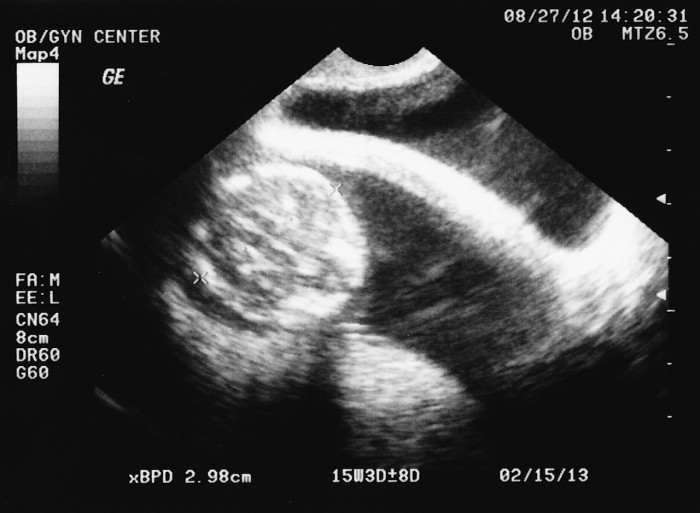

2012-08-27-Ultrasound-05-web Post author By sean Post date October 13, 2012 No Comments on 2012-08-27-Ultrasound-05-web Leave a Reply Cancel replyYour email address will not be published. Required fields are marked *Comment * Name * Email * Website